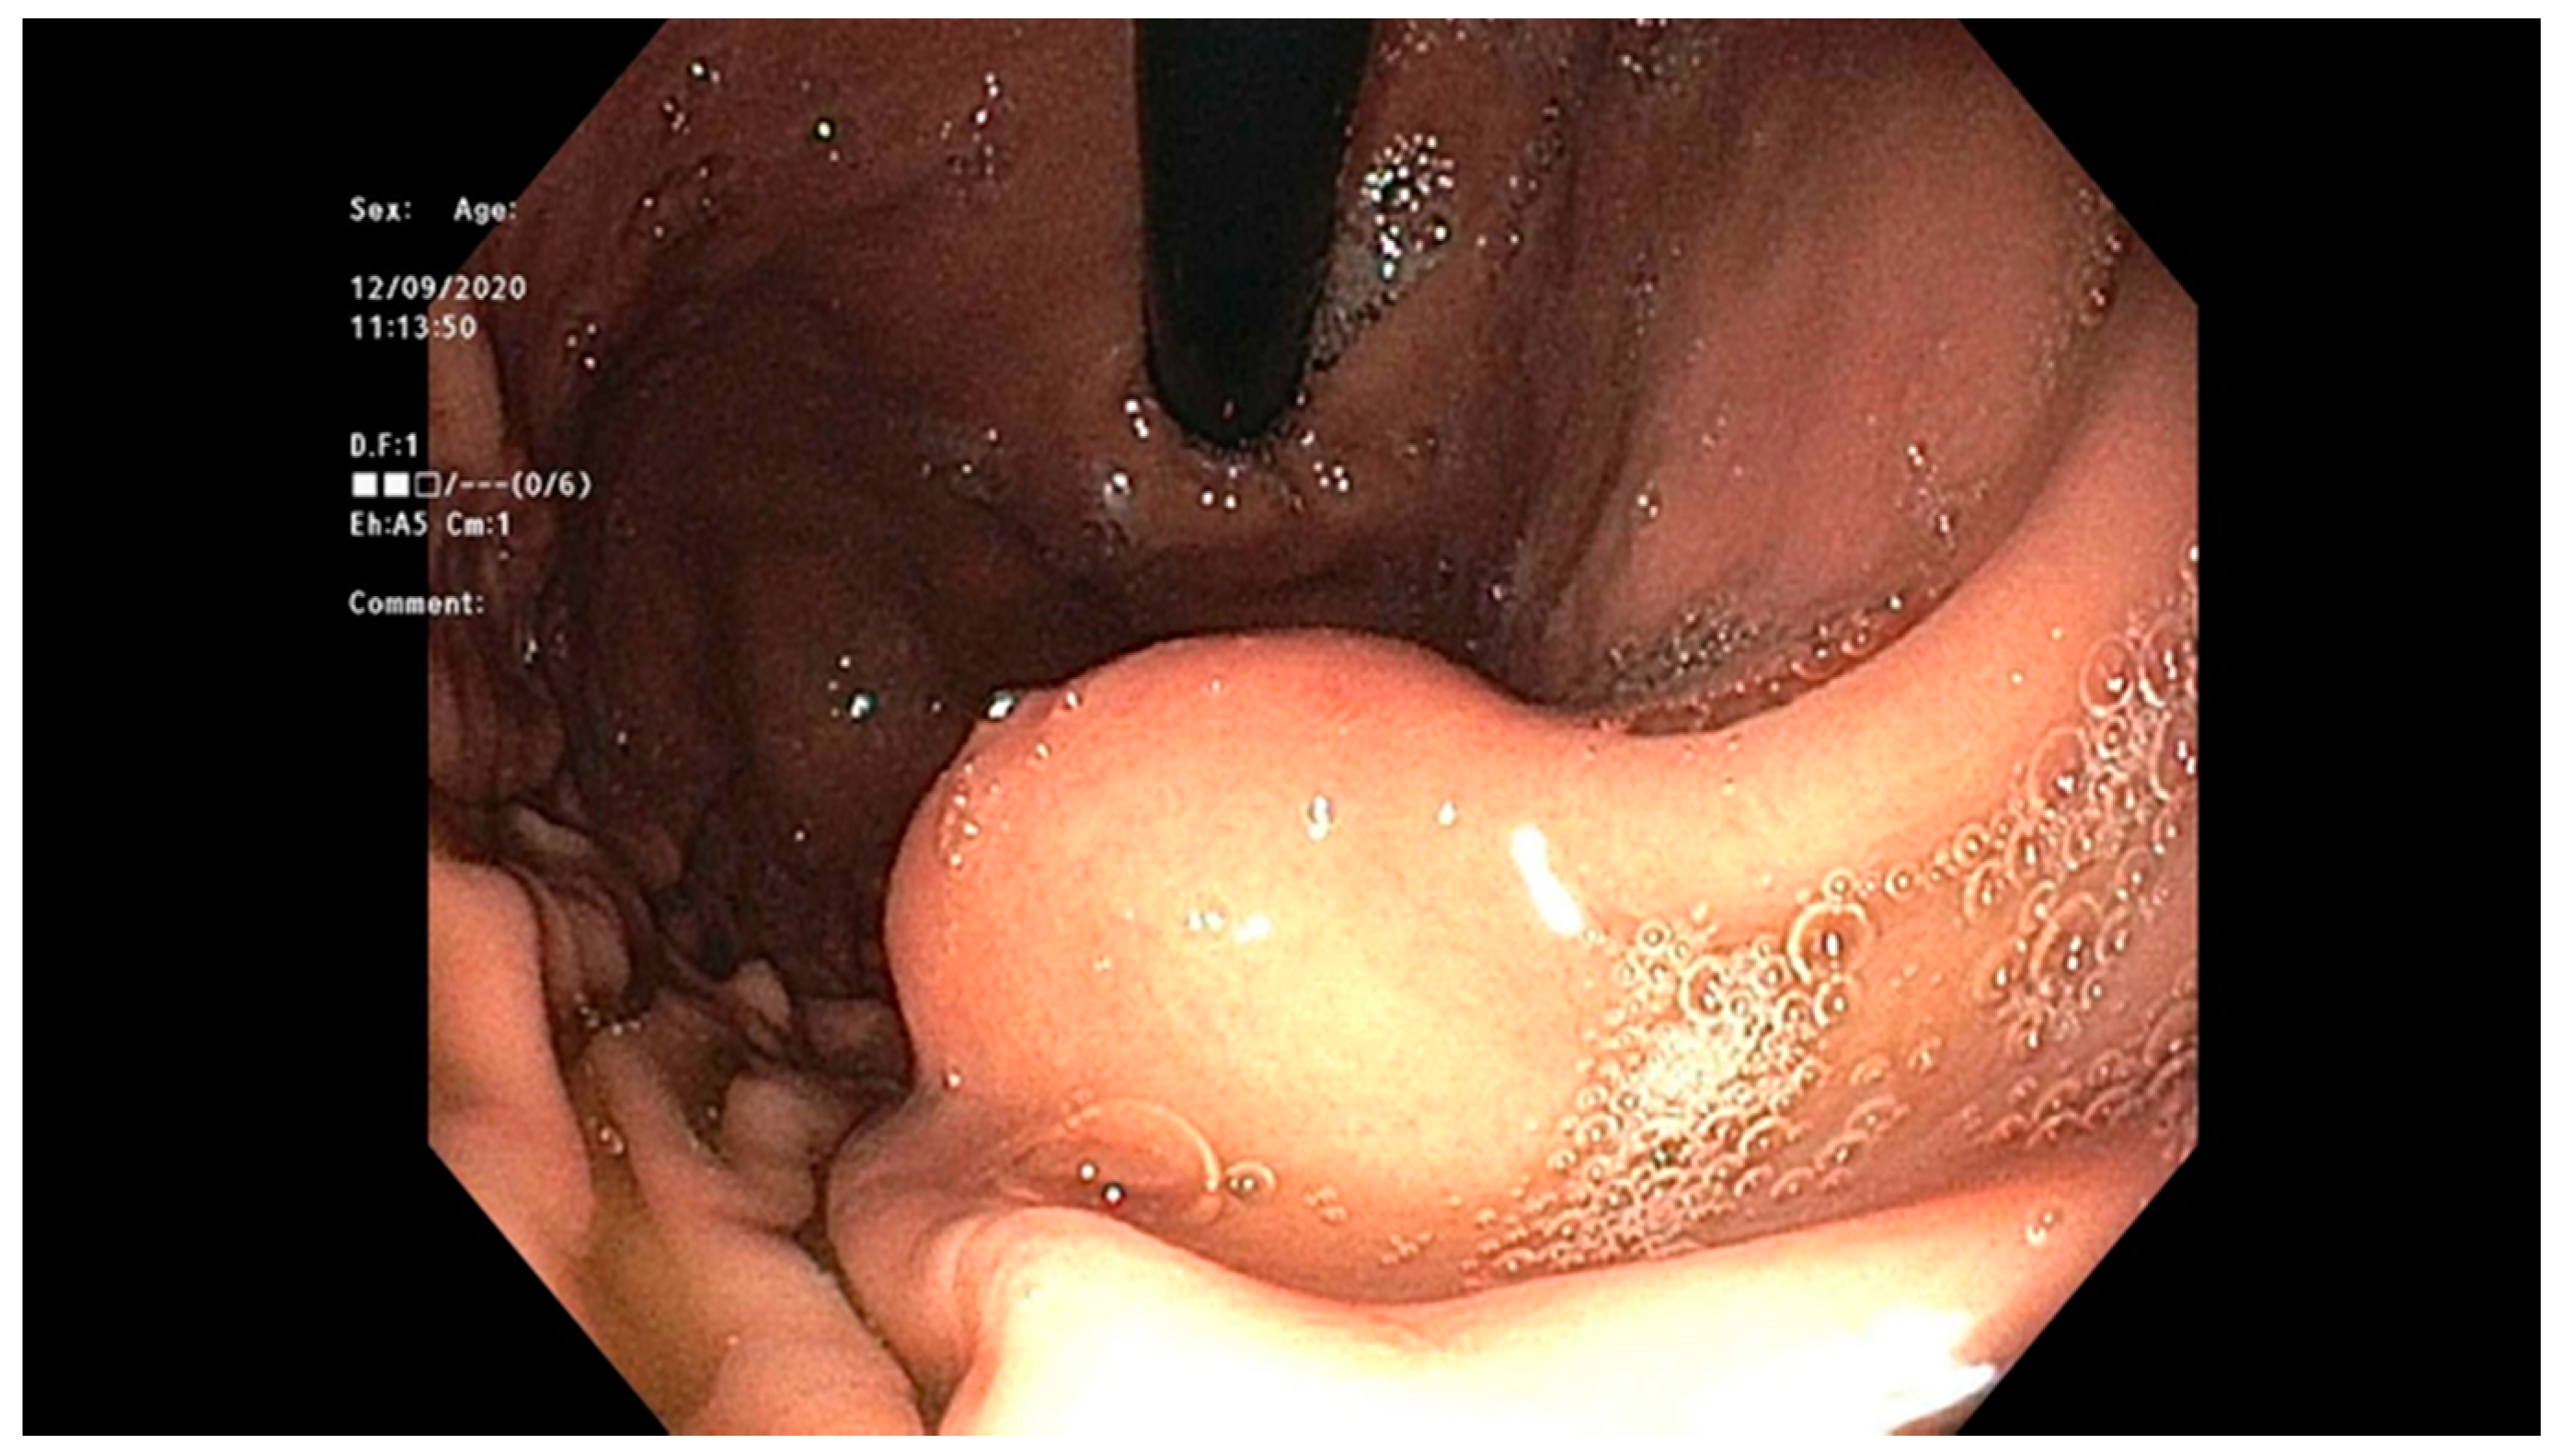

4.2. Early Gastric Cancer (EGC)

- Waddingham, W.; Nieuwenburg, S.A.V.; Carlson, S.; Rodriguez-Justo, M.; Spaander, M.; Kuipers, E.J.; Jansen, M.; Graham, D.G.; Banks, M. Recent advances in the detection and management of early gastric cancer and its precursors. Front. Gastroenterol. 2020. [Google Scholar] [CrossRef]